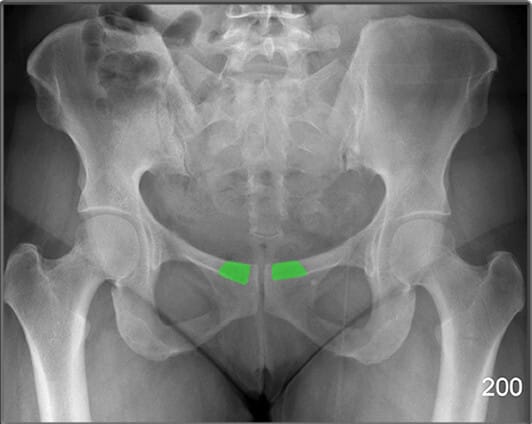

상치골지 (Superior Pubic Ramus)

| 상치골지 (Superior Pubic Ramus) |

| ✅ 치골의 상단 분지로, 치골결합에서 대각선으로 위쪽으로 뻗어 장골과 연결됩니다. AP View에서는 골반 앞쪽 상부에서 연속적인 골 음영으로 나타납니다. |

| 🔴골반 고리의 안정성을 평가하는데 중요한 구조입니다. |

하치골지 (Inferior Pubic Ramus)

| 하치골지 (Inferior Pubic Ramus) |

| ✅ 치골의 하부 분지로, 좌골과 연결되어 골반 하부를 구성합니다. AP view에서 치골결합 아래쪽에서 대각선 방향으로 연장된 음영으로 나타납니다. |

| 🔴 외상성 골절이 흔히 발생하는 부위입니다. |